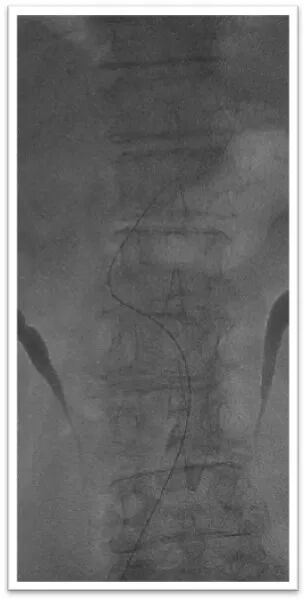

该患者胸主动脉迂曲,主动脉弓呈牛角弓,选择5F 125cm蒸汽塑形后在泥鳅导丝引导下同轴引导6F Neuron Max长鞘顺利置于左侧颈总动脉;

采用ADAPT技术长鞘直接抽吸

将6F Neuron Max长鞘抵近血栓近端后持续负压吸引抽出部分暗红色血栓,造影显示血栓完全栓塞颈总动脉分叉处,颈内动脉C1段可惨淡显影,由于路径迂曲长鞘长度受限,无法完全抵近血栓核心。